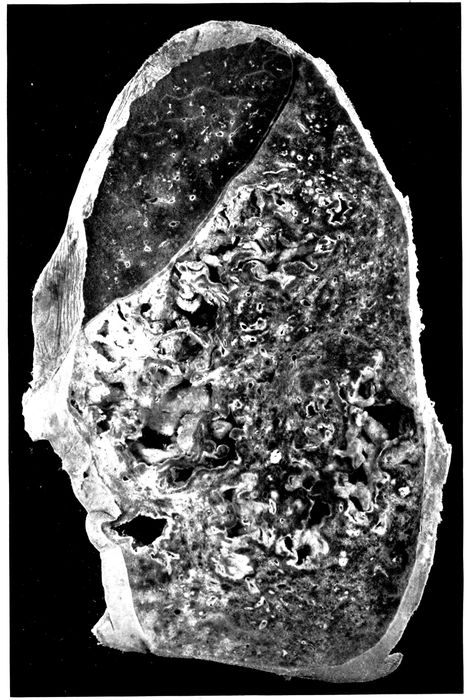

| 6. | Acute bronchopneumonia with confluent gray lobular consolidation in lower part of upper lobe and hemorrhagic peribronchiolar pneumonia in lower lobe; purulent bronchitis | 180 |

| 7. | Bronchopneumonia with purulent bronchitis and peribronchial hemorrhage | 190 |